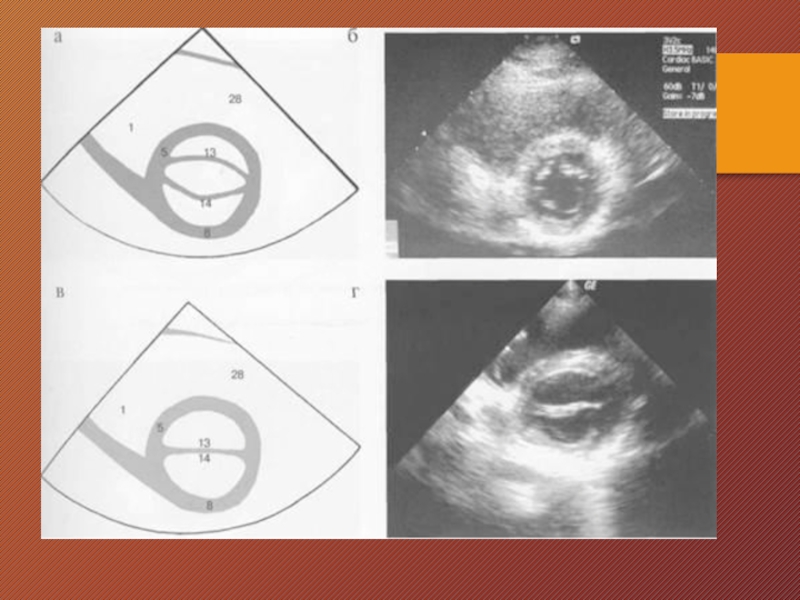

Слайд 23Для получения парастернального поперечного сечения на уровне митрального клапана сердце

луч отклоняют влево. В этом сечении большую часть изображения занимает левый желудочек, в центре которого визуализируются передняя и задняя створки митрального клапана. В верхней части изображения оказывается часть правого желудочка, между правым и левым желудочками — межжелудочковая перегородка. Для получения парастернального поперечного сечения на уровне папиллярных мышц сохраняется прежнее положение датчика, но центральный ультразвуковой луч

ориентируют несколько книзу. В этом сечении в центре изображения (рис.) также оказывается левый желудочек, в его полости видны переднелатеральная и заднемедиальная папиллярные мышцы.

Для получения парастернального поперечного сечения на уровне митрального клапана сердце сканируют так же, как в предыдущем случае,